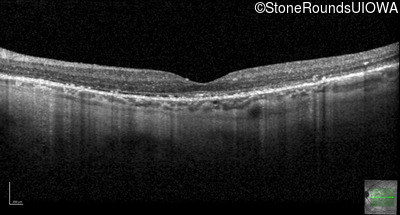

Optical Coherence Tomography - Left - 20/20 -2

Exemplar / OCT Stack